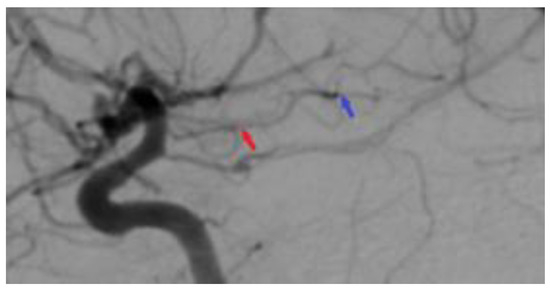

Figure 6.

Postoperative 2D DSA. The image represents a normal diameter of the anterior choroidal artery (red arrow), with the total ablation of the right temporal arteriovenous malformation being achieved (blue arrow).

A follow-up non-contrast CT scan displayed a region of deep right fronto-temporal hypodensity, indicative of a post-surgical sequelae (Figure 4). Additionally, the CT scan identified areas of hemorrhage, which were deemed not to require further surgical intervention (Figure 5). Subsequent control angiography of the right carotid artery confirmed the complete excision of the AVM, with the preservation of the pathway of the right anterior choroidal artery (Figure 6). The patient was then managed with conservative treatment, resulting in a favorable clinical progression and substantial neurological improvement. After 2 weeks of hospitalization, at the time of discharge, the patient’s left hemiparesis had improved to 3/5 on the Medical Research Council (MRC) scale and assigned GCS was 12 points (eye response—3 points, verbal response—4 points, motor response—5 points).